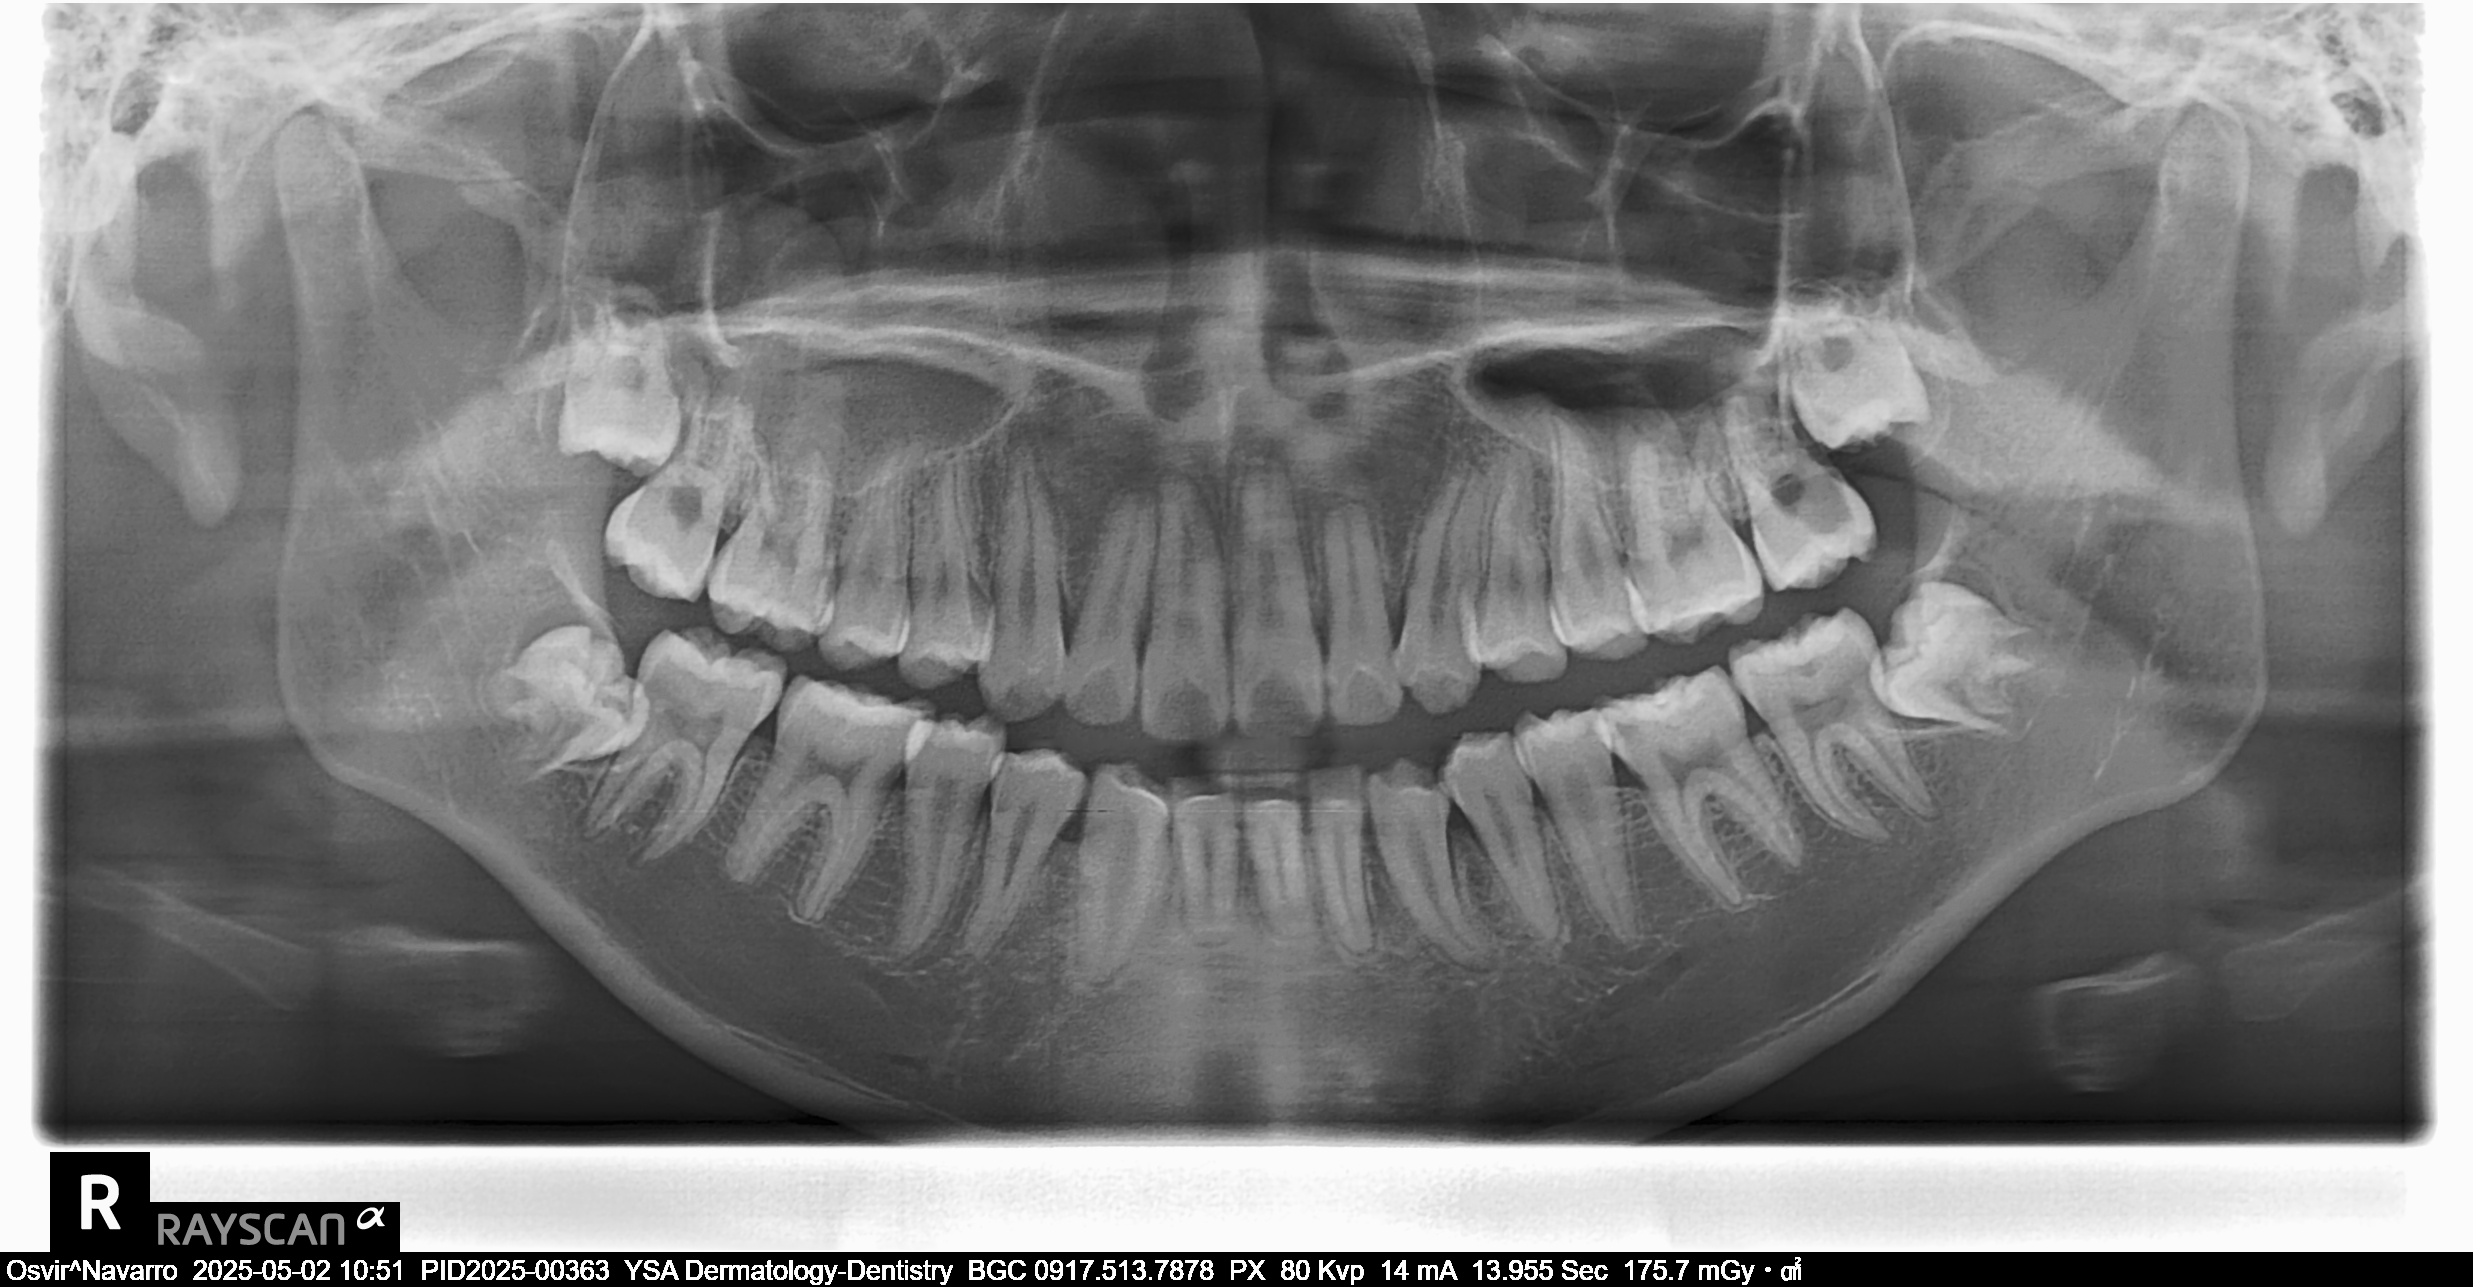

Edit Record Check our patient data records. Add patient information Patient Info Profile picture Last Name First Name Middle Name Birthdate Age Street Barangay City Country Zip Code Contact number Email Procedure 5/21/22- OP & LC #26 OB #36 OL 4/29/23- Exo/Sealant3/ 07/05/23-impression intra oral photos OP (no extra oral photos yet) 07/11/23- /installation upper braces/roth .22 niti 14 niti Frenectomy- diode laser/tongue tie 07/25/23- Installation of lower brackets 14 nit LC #37-Occ #47-Occ + Buccal #24-Occ 08/08/23- adjust 09/02/23- adjust 10/07/23- 18 Niti U/L reposition #23 11/11/23- 16 SS Upper 16 SS Lower, Chain #41-32, Extrude #33 12/22/23- 18 niti U with wire bendings on 21/ 22/23 same wire lower 03/16/24 same wire RW #12 04/12/24 New Bt #36 Adj 16 SS U 18 SS L RW #33- distal 05/18/24 adj 16x16 NiTi L 16x16 SS U elastic rabbit 06/15/24 same wire IPR #11/21/22/12 class II elastic chipmunk 07/16/24 16X22 SS U 16 NITI L 08/10/24 #45 new bracket 16 SS L same wire chain U 09/07/24 16x16 SS L class III elastic chipmunk 10/12/24 ADJ chain upper new buccal tube #36 tentative removal; march/april 11/09/24 same wire chain upper 12/20/24 new buccal tube #26 reattach #25 (new) rabbit 3.5 oz 01/25/25 adj same wire cross elatic-penguin 2nd pm to 3rd 02/22/25 Adj canine to canine chipmunk posterior to posterior rabbit 5oz 03/29/25 Adj crimpable hook class II elastic rabbit 5oz for removal nxt month 04/26/25 removal brace w/ free retainer 05/17/25 ODontectomy #18,48 w/ IV CS Rx: clindamycin 300mg/ celecoxib 05/23/25 suture removal 06/03/25 Odontectomy #28,#38 Rx: prednisone. B complex, celecoxib 200mg, IV CS 06/10/25 LC #22 Mesial,facial 05/05/26 OP varnish File jaunne_osvir.jpg File 2 file_0001_2_1.jpg File 3 1000006361.jpg File 4 1000006360.jpg File 5 1000006359.jpg File 6 1000006358.jpg File 7 1000006354.jpg File 8 1000006353.jpg File 9 File 10 File 11 File 12 File 13 File 14 File 15 File 16 File 17 File 18 File 19 File 20 Retain Record Retain Record Yes No Save Your Changes